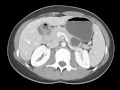

Mucinous Cystic Neoplasm

Multiple MR images demonstrate a T2 bright cystic mass arising from the pancreatic tail. This mass was found to represent a mucinous cystic neoplasm